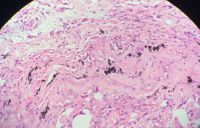

有人知道片子中的为何种异物?

常规片子与免疫组化是两个病例!异物颜色也不一样

这不是苏木素吗?

• andelionDD:  我也觉得是苏木素沉渣,可是换了另外一家医院染色,还是有

苏木沉淀物,过滤。

先把染料过滤了看看还有没有,

另,标本固定的时间要是长了需水洗干净,否则会有福尔马林色素,图1就很像。

这个是苏木素的沉淀,过滤一下应该就可以了!